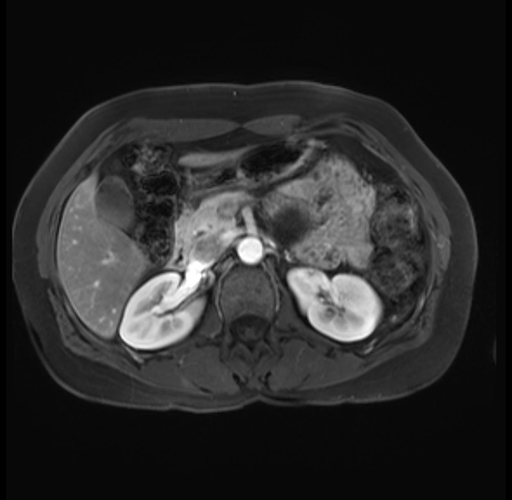

Imaging Analysis

Look through the patient's CT scan to identify any areas of concern for the necessary procedure.

Based on your CT findings, which issue(s) are present and would give reason for "planned slowing down moment(s)" in this case?